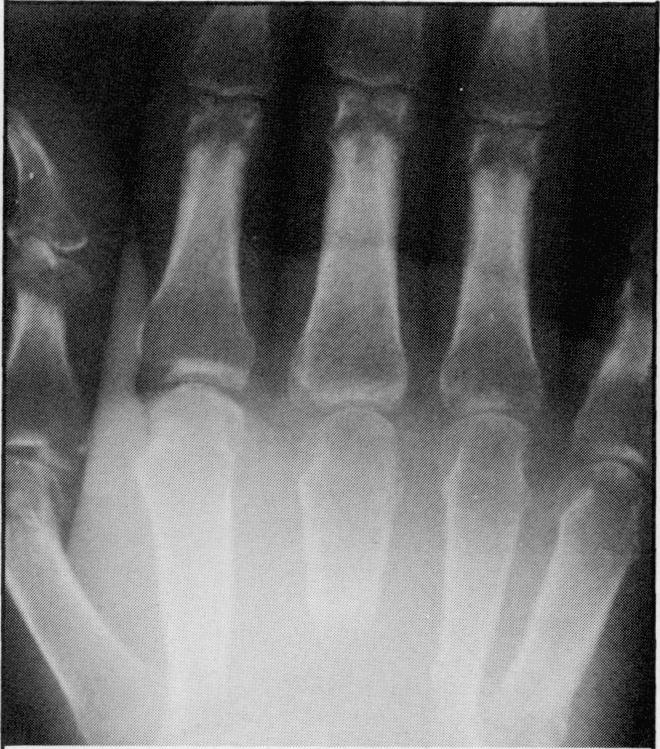

Although metastases to bones from solid tumors are very common, involvement of small bones of the hands and feet is extremely rare. One half of the cases reported in literature resulted from a primary tumor in the lung. Four cases seen over the last four years with metastases to bones of the hand and one case with metastases to foot bones are discussed. None of these patients had a lung primary tumor. Three of the four patients who had metastases to hand bones had the disease on the right side.

尽管实体瘤骨转移很常见,但手足小骨受累极为罕见。文献报道的病例中有一半源于原发性肺癌。本文讨论了过去四年中见到的4例手部骨转移病例和1例足部骨转移病例。这些患者均无原发性肺癌。4例手部骨转移患者中有3例病变位于右侧。